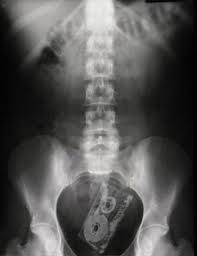

Kazayla Giren Nesneler